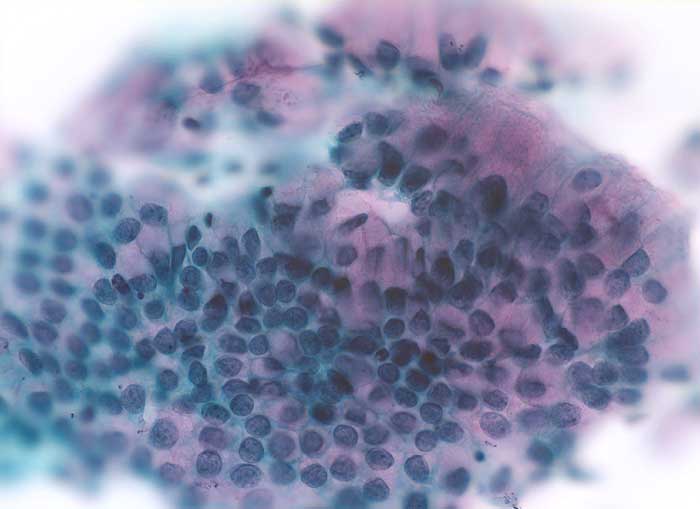

Reaktive Veränderungen bei Intrauterinpessar

Im Abstrich von Patientinnen, die eine Intrauterinpessar (IUP) zur Kontrazeption tragen, können zu jedem Zeitpunkt des menstruellen Zyklus Endometriumzellen nachgewiesen werden. Ausserdem finden sich oftmals atypische glanduläre Zellen und dies auch noch Monate nach Entfernung des IUP. Es existieren drei Typen von atypischen Zellen, die assoziiert sind mit einem IUP: hypervakuolisierte endozervikale Zellen, vakuolisierte metaplastische Zellen und endometriale Zellen, die einzeln oder in Gruppen gelagert sind. Im Gegensatz zum Adenokarzinom zeigen die reaktiv veränderten Epithelien keine malignen Kerne und keine Tumordiathese. Im Gegensatz zum Carcinoma in situ sind nur wenige atypische Zellen mit blandem Chromatin vorhanden. Bei Patientinnen mit IUP treten ausserdem gehäuft Infektionen mit Aktinomyceten auf. Bei Dysplasien im metaplastischen Epithel und Atypien im Zylinderepithel wird die Entfernung des IUP und eine erneute zytologische Kontrolle nach 3 Monaten empfohlen. Persistierende zytologische Veränderungen sollten histologisch weiter abgeklärt werden.